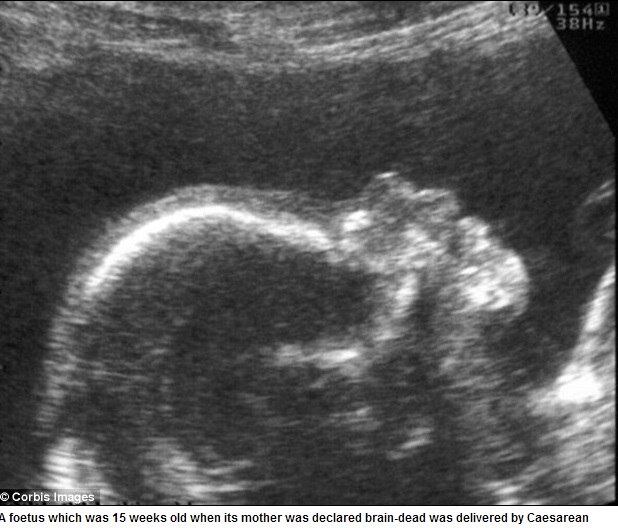

A mãe sofreu um derrame no cérebro na 15ª semana de gravidez e teve morte cerebral, mas os médicos mantiveram suas funções vitais ativas até que em julho o bebê nasceu por cesariana, após sete meses de gravidez.